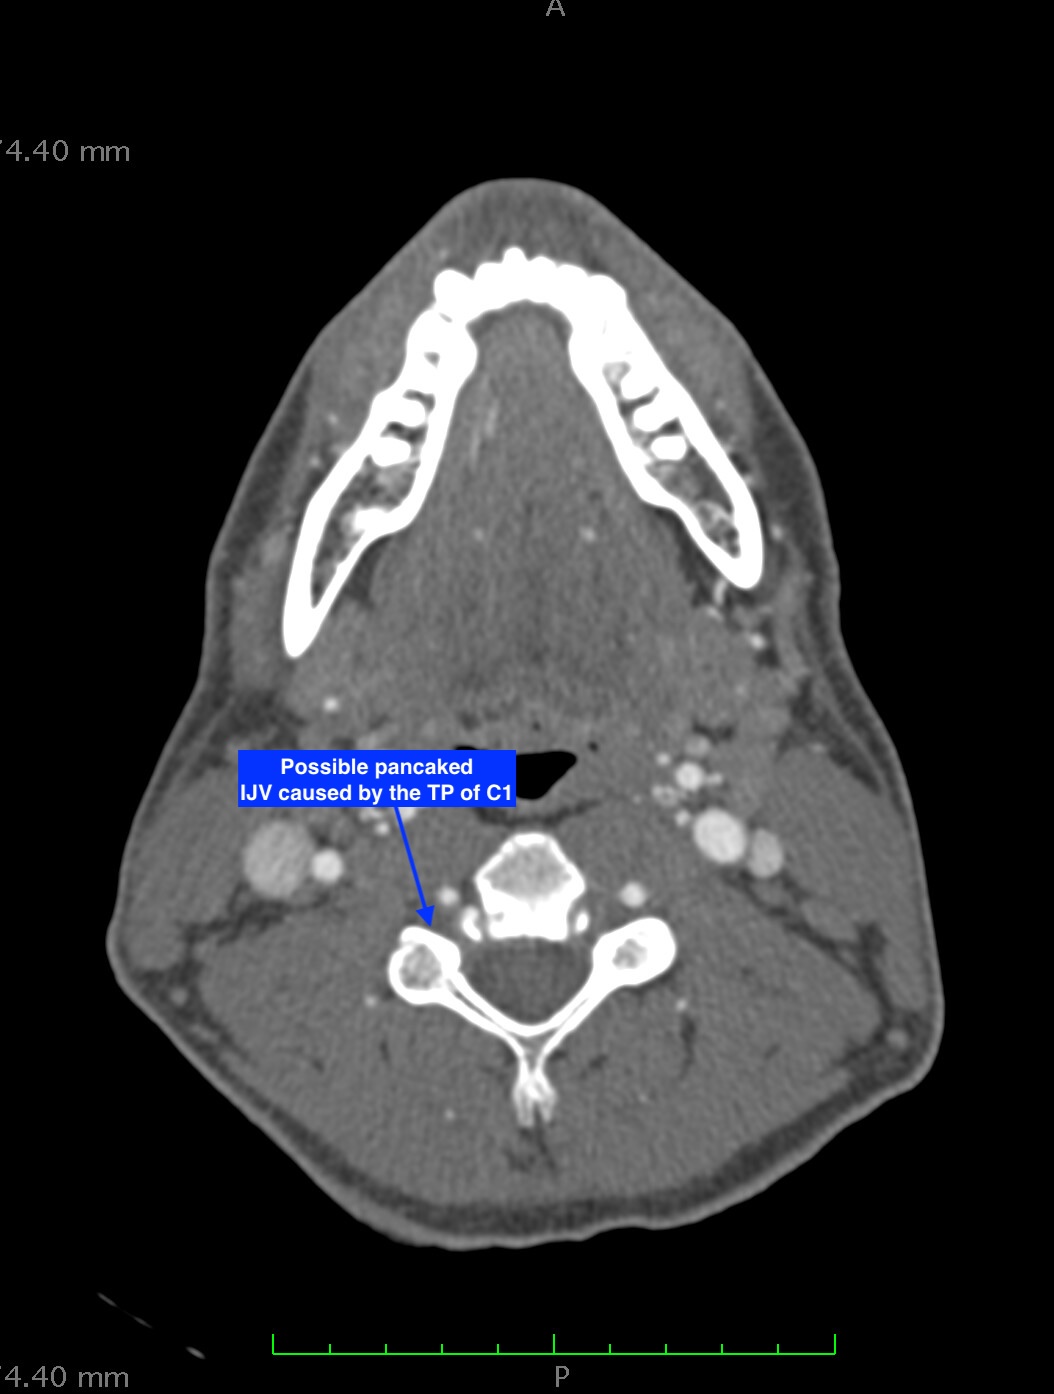

From your current description, I’d say you have internal jugular vein compression possibly being caused by your styloid/C1 & based on the pictures you posted, more by C1 (I’m assuming the sagittal image is your right side). With your note that your right external carotid artery is in the wrong place, I suspect you may also have ICA/ECA irritation/compression being caused by the right greater horn of your hyoid. The issue more likely is that the right greater horn of your hyoid is elongated & has come between your ICA & ECA just above the carotid bifurcation. We’ve been seeing more of this recently as well as having more members who seem to have symptoms & scan evidence of both ES & HBS.

I’ve annotated a couple of your images but please don’t take my guesses as diagnostic. You have lost the lordotic curve in your cervical spine which can also contribute to the symptoms you have by bringing the styloids & hyoid closer to the nerves & vascular tissues in your neck thus increasing the chance they will “meet” in an unfriendly way. There are gentle PT exercises that can help restore the curve (see the link below) or explore the Denneroll (Cervical Combination Order).